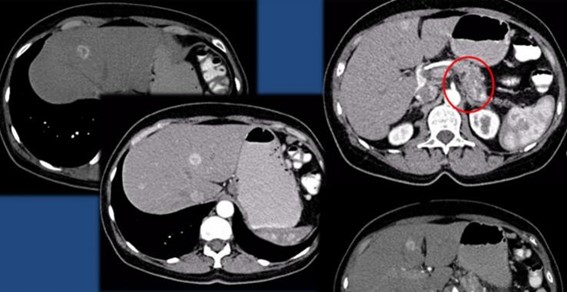

Las recomendaciones estándar para el diagnóstico de CHC incluyen TC multifásica o RMN, que son modalidades beneficiosas para resaltar características únicas de CHC (Anexos 12 y 13). Las diferencias fisiológicas en la perfusión sanguínea entre lesiones hepatocarcinogénicas y tejido no neoplásico muestran diferencias distintivas en las características de imagen utilizando exámenes de contraste multifásico.(23) Las fases consisten en arterial hepática tardía (20-40 s), venosa portal (60-90 s) y retardada (35 min). La fase arterial tardía es útil para detectar lesiones hipervasculares con lesiones de CHC que realzan característicamente en relación con el parénquima hepático circundante. El realce de la lesión arterial se puede apreciar dentro de lesiones tan pequeñas como 1 cm. Dentro de las fases venosa portal y retardada, se observa comúnmente lavado o hipointensidad para las lesiones de CHC. Durante la fase retardada o de equilibrio, se pueden visualizar otras características de CHC como características de la cápsula (p. ej., lavado de la lesión con realce de seudocápsula) y arquitectura en mosaico. La introducción de agentes de contraste basados en gadolinio (gadobenato de dimeglumina y ácido gadoxetato) puede ayudar a la categorización LI-RADS.(19) Estos agentes son absorbidos por los hepatocitos del parénquima hepático normal y hay poca absorción en hepatocitos no funcionales o disfuncionales, como el caso del CHC. Los agentes basados en gadolinio funcionan de manera similar a los agentes extracelulares, pero pueden ayudar en el diagnóstico de lesiones con características atípicas (p. ej., sin lavado, hiperrealce arterial) o distinguir el CHC de las seudolesiones. Por ejemplo, estos agentes permiten una fase hepatobiliar posterior al contraste adicional, que mostrará una mayoría de lesiones de CHC (90%-95%) como hipointensas en relación con el parénquima hepático hiperintenso circundante.(23)

Se recomienda la RMN para la estadificación de la enfermedad de CHC, dado que algunos informes han estimado que la TC subestima el 52% de los casos.(23) La RMN también tiene una eficiencia diagnóstica superior a la TC en la detección de lesiones pequeñas (≤ 3 cm). Sin embargo, la TC está más fácilmente disponible que la RMN, y las limitaciones para usar la RMN, incluidos mayores costos y complejidad técnica, hacen de la TC una alternativa diagnóstica complementaria. Un informe mostró que el uso combinado de TC/RMN proporciona una mejor precisión diagnóstica en la caracterización de lesiones hepáticas utilizando LI-RADS (91,29%) que la RMN (85,37%) o la TC (67,6%) solas, pero los protocolos combinados deben limitarse a casos difíciles o inciertos para justificar su uso.(21-23)